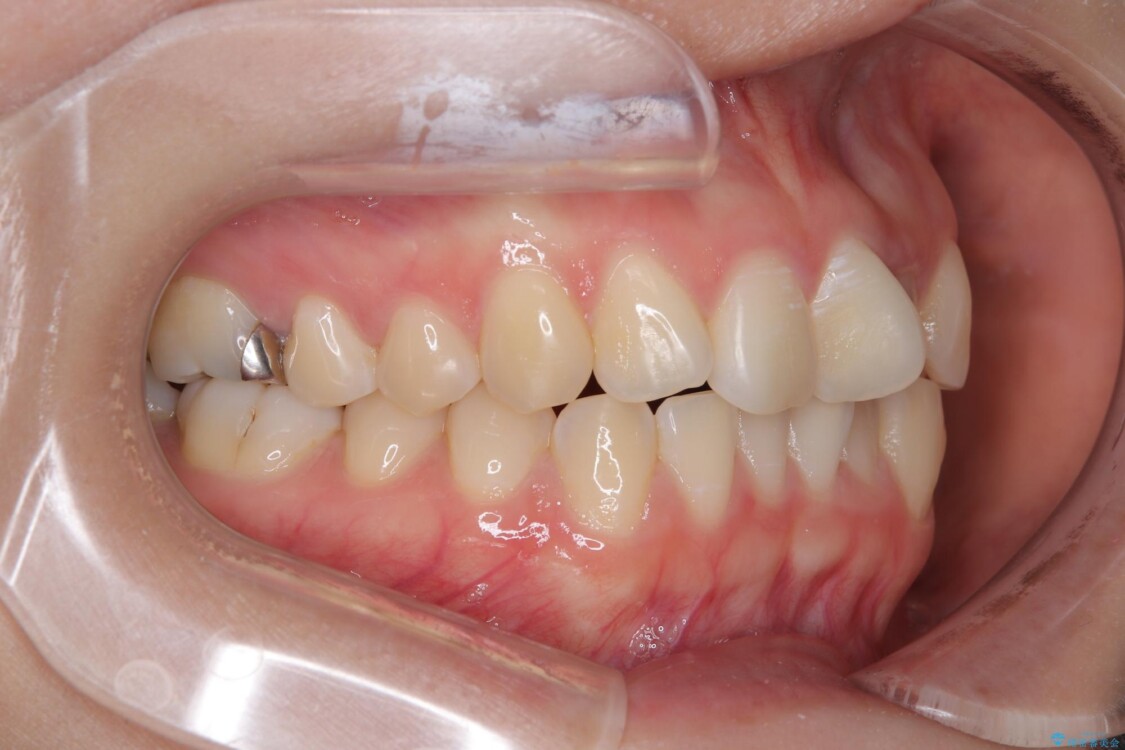

診察の結果、上下の前歯部に**叢生(そうせい/歯のガタガタ・重なり)**が認められました。

特に上の前歯にはねじれや重なりがあり、審美的にも清掃性にも影響している状態でした。

治療前

• 前歯のねじれ・ガタガタを10か月で改善!20代女性の矯正治療|クリアブラケットでむし歯になりにくい歯並びへ改善 治療前画像